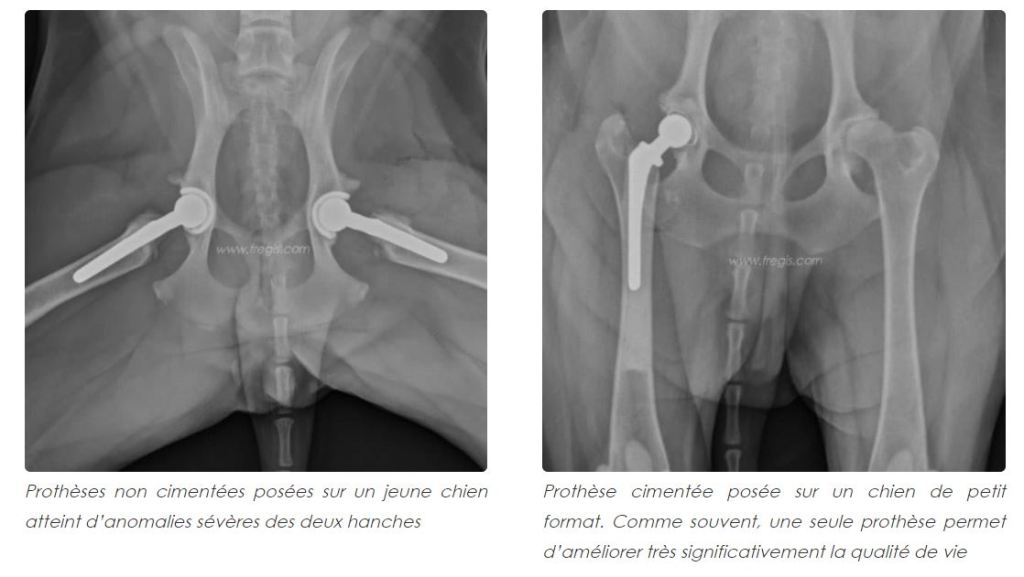

- Une prothèse de hanche: Elle est recommandée pour les chiens pour soulager la douleur et / ou l’invalidité associée à une maladie de la hanche, le plus souvent lors de dysplasie coxo-fémorale.

Si la dysplasie de hanche est bien suivie et que les bonnes décisions sont prises au fur et à mesure de l’évolution, un chien dysplasique peut vivre une vie entière, avec une bonne qualité de vie.

90% des triples ostéotomies de bassin (TOB) pratiquées au bon âge et sur un bon candidat, conduisent à un bon résultat (boiterie rare). Il en est de même pour la prothèse de hanche.